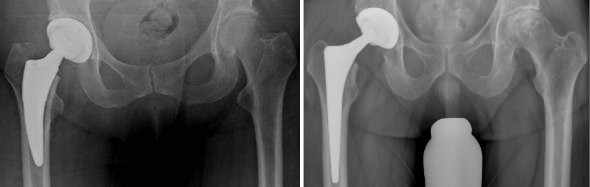

Wir halten ein großes Portfolio moderner und bewährter Prothesen vor, die sich im Prothesendesign unterscheiden. Innerhalb des Designs liegen verschiedene Ausführungen und unterschiedliche Größen vor. Auf der Schaftseite unterscheiden wir Kurzschaft, Geradschaft, anatomischer Schaft und modularer Schaft. Auf der Pfannenseite verwenden wir moderne „Press-fit-Pfannen“, die sich primär im Knochen verklemmen und sekundär vom Körper in den Knochen integriert werden. Defektsituationen können entweder durch Verwendung von Fremdknochen aus der von uns geführten Knochenbank oder durch Implantation von Tantal-Augmentaten behandelt werden.

Die Standardversorgung ist, abhängig von Alter und Knochensubstanz, die zementfreie Implantation von Schaft und Pfanne. Bei weicherer Knochenkonsistenz verwenden wir eine sogenannte „Hybrid-Verankerung“; gemeint ist die zementfreie Pfannenverankerung bei zementiertem Schaft. In Ausnahmefällen wird bei besonders weicher Knochensituation die Prothese komplett zementiert. Falls bei Ihnen Allergien nachgewiesen wurden, finden hypoallergene („allergiefreie“) Implantate Anwendung.

Während des Eingriffes wird Ihr Gelenk gegen ein künstliches Gelenk ausgetauscht. Der Eingriff dauert in aller Regel ein bis eineinhalb Stunden und kann in Allgemein- oder Teilnarkose durchgeführt werden. Welche Art der Narkose für Sie in Frage kommt, wird Ihr Narkosearzt mit Ihnen besprechen. Durch das prä- und intraoperative Blutmanagement der Anästhesieabteilung werden Fremdblutkonserven normaler Weise nicht benötigt. Am ersten postoperativen Tag werden Sie auf die Normalstation verlegt, wo mit der Mobilisierung begonnen wird. Während des stationären Aufenthaltes werden Sie einen sicheren und selbständigen Gang wiedererlernen – in der Regel ohne Belastungseinschränkungen. Die Entlassung erfolgt, wenn Wund- und Weichteilverhältnisse regelhaft abgeheilt sind, Sie einen sicheren Gang erlernt haben, und keine medizinischen Gründe gegen eine Entlassung oder eine Verlegung zur Anschlussheilbehandlung sprechen.